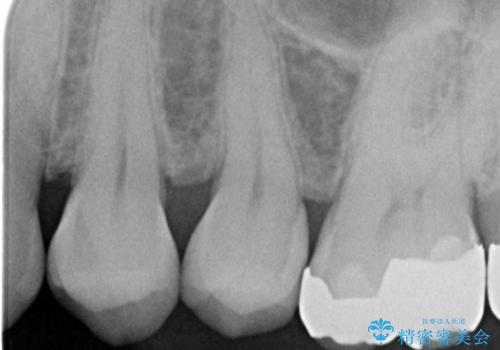

銀の詰め物を拡大鏡下で取り除き、う蝕がないことを確認してから

ZrCrの被せ物で治療を行いました。

また、一つ手前の歯に小さな虫歯があったため

e-maxインレーでの治療を行いました。

銀の詰め物の範囲が大きいほど

やりかえをする時、セラミックの詰め物だと割れるリスクがあるため

ZrCrの被せ物のご案内をする事があります。